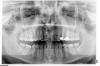

an_ver Опубликовано 19 июня, 2013 Поделиться Опубликовано 19 июня, 2013 Предистория такая.....П-ка обратилась к ортодонту по поводу (выступающего) клыка (23).Было проведено снятие слепков, ТРГ, ОПТГ не делалось,выставили 24, залепили Даймон на в/ч, через 8-9 месяцев готово((((. Обратилась ко мне через 2 года....ц.линия ушла (а может ее и не было) в суставах дискомфорт....Что думаете по этому случаю,коллеги? П-ка хочет все красиво Ссылка на комментарий

Премоляр Опубликовано 19 июня, 2013 Поделиться Опубликовано 19 июня, 2013 (изменено) Одностороннее удаление всегда предусматривает асимметрию и последующее сужение в.ч....суженная в.ч. блокирует н.ч.,вызывая(или не вызывая) так называемую "дисфункцию ВНЧС" Без соответствующего симметричного удаления симметрию не получить. Удалив 14 например,ср.линию "вернем на место ", но еще более уменьшим в.ч.,еще больше заблокируем н.ч.Соответственно,потребуется семметричное удаление и на н.ч....и т.д..Разумеется,возможно восстановить симметрию за счет создания места для 24. Это возможно.П.с. Деймон,8 мес.,одностороннее удаление,лечение на одной челюсти...Классика жанра. Сразу готовят пациента к перелечиванию Изменено 19 июня, 2013 пользователем Премоляр 3 Ссылка на комментарий

Викторовна575 Опубликовано 5 июня, 2014 Поделиться Опубликовано 5 июня, 2014 В результате одностороннего удаления произошло уплощение переднего отдела верхней зубной дуги, преимущественно слева,соответственно суставная головка левого ВНЧС еще больше сместилась дистально,создавая компрессию на биламинарную зону,отсюда и дискомфорт в области ВНЧС,я бы удалила 8-е на в\ч ,по крайней мере справа-точно,раскрыла промежуток для 14,чтоб восстановить симметрию в/ч,выровнить окклюзионные кривые,тяги-саморотация н/ч,даже если сохранится небольшая сагиттальная щель-для сустава это более благоприятно,а вообще, хорошо б еще КТ ВНЧС Ссылка на комментарий